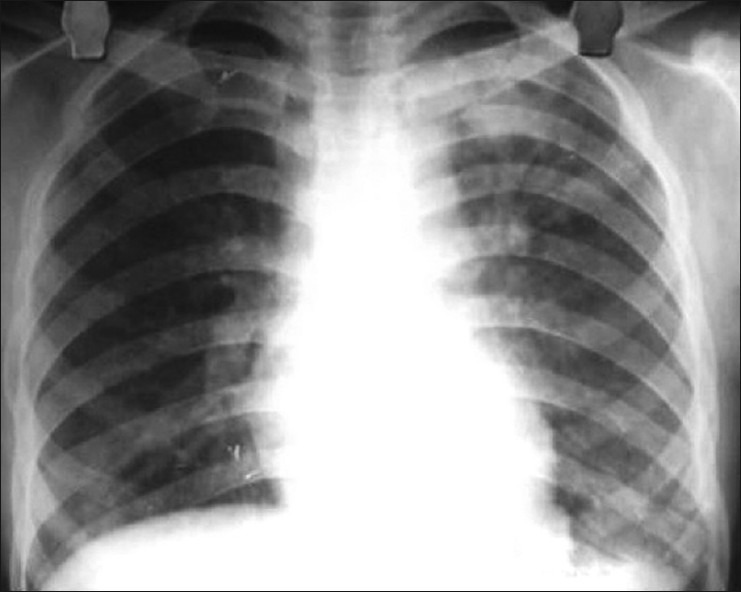

То, как выглядит туберкулез на рентгеновских снимках, непосредственно определяет вид этого заболевания.

Выделяют следующие рентгенологические типы туберкулеза:

• инфильтративный;

• кавернозный;

• фиброзно-кавернозный;

• диссеминированный;

• цирротический;

• первичный туберкулез.

Инфильтративная форма

Это наиболее распространенная форма туберкулеза, которая встречается более чем в 60 % случаев. Она характеризуется распространенным некрозом (гибелью) ткани легкого. В зависимости от того, что показывает флюорография легких, выделяют несколько подтипов инфильтративного туберкулеза:

• круглый инфильтрат — затемнение овальной или округлой формы в верхних отделах легких, чаще всего под ключицей;

• облаковидный инфильтрат — тень однородной структуры с неровными границами;

• краевой инфильтрат — тень имеет форму треугольника, вершина которого направлена к корню легкого;

• дольковый инфильтрат — представляет собой группу слившихся очагов различной плотности;

• лобит — тень больших размеров, охватывающая целую долю легкого, имеет неоднородную структуру.